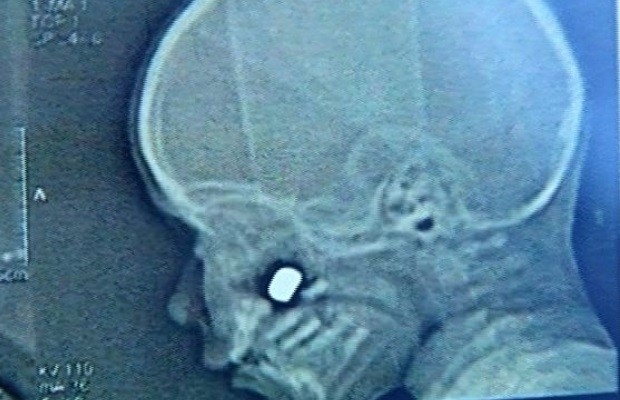

O pai do menino de 2 anos baleado no rosto, em Anápolis, a 55 quilômetros de Goiânia, é autor do tiro que atingiu a criança. Inicialmente, a mãe relatou à polícia que o garoto havia sido vítima de um ladrão. Mas, na tarde de quinta-feira (16), Lucas Francisco Pires confessou ter disparado acidentalmente e atingido o filho, informou o delegado Éder Ferreira, responsável pelo caso